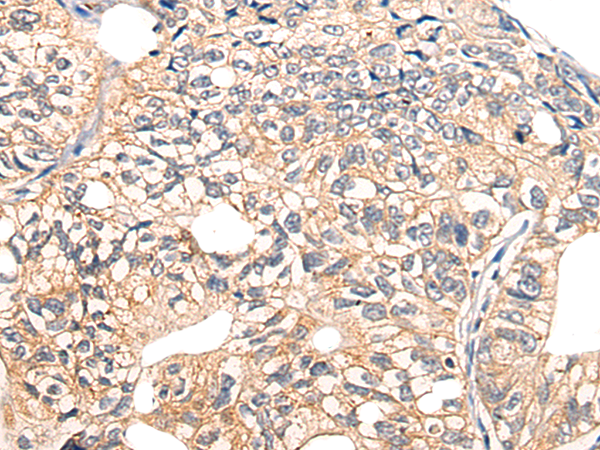

IHC positive control:

Human gastric cancer

IHC Recommend dilution:

10-50